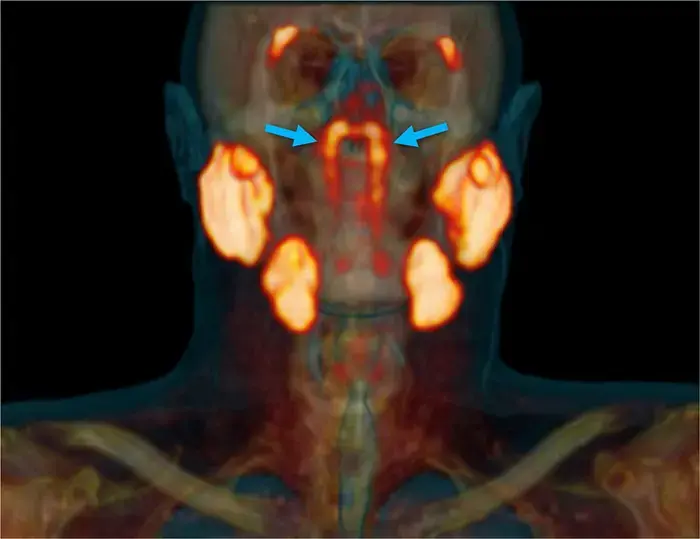

Исследователи из Нидерландского института рака обнаружили в теле человека новый орган. Он находится в центре головы — это четвертая пара крупных слюнных желез, пишет Science Alert.

Неожиданное анатомическое открытие было сделано случайно во время ПЭТ-КТ-диагностики пациента с раком простаты.

Медики заметили слюнные железы там, где их не должно было быть – почти в центре головы, в глубине носоглотки за трубным валиком. Исследователи назвали эти железы трубными (tubarial) из-за их анатомического расположения.

Присутствие четвертой пары слюнных желез ученые подтвердили дополнительным сканированием ПЭТ-КТ на около сотне пациентов, а также при вскрытии двух тел — мужского и женского

Авторы исследования предполагают, что эта пара желез обеспечивает смазку и защиту носоглотки и зева.